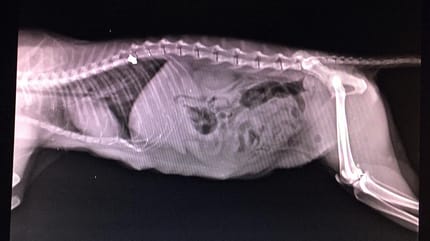

Radiographie du ventre d'un chat

© Huellas de Sarria / Facebook

La radiographie révèle alors qu'une balle est logée dans sa colonne vertébrale. Il est immédiatement clair que le chaton doit être opéré pour déterminer si ce corps étranger est la cause de l'incapacité de Fiuncha à bouger.